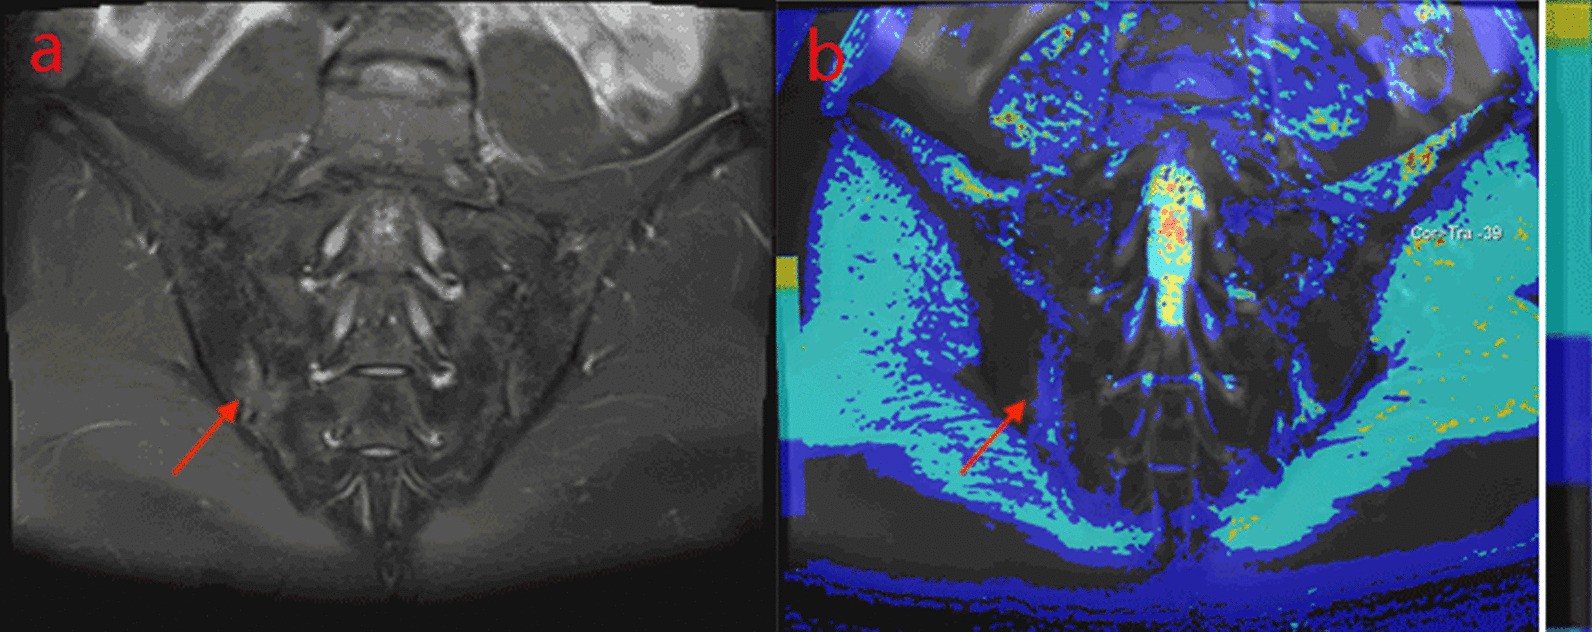

Fig. 1

A male, 32 years old, HLA-B27: + , ASDAS-CRP:1.9, belongs to the moderate activity group. a The coronal plane of PDWI shows high signal intensity of bone marrow under right sacroiliac articular surface. b T1-mapping pseudo-color diagram demonstrates the T1-mapping values of regions of interest is 519.27 ms